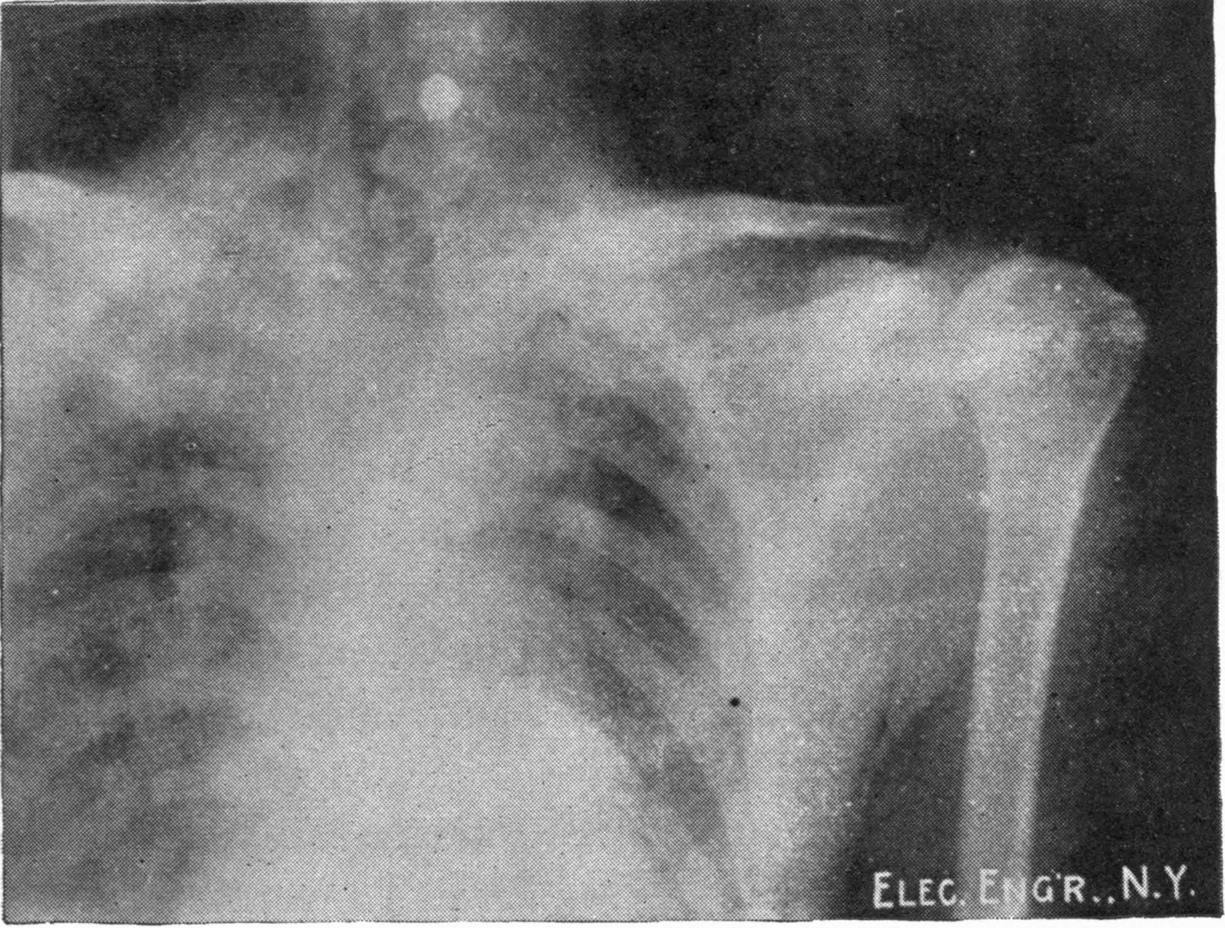

Fig. 3.—Ribs.

Fig. 4.—Knee, Knickerbocker Buttons, Bullet in Femur.